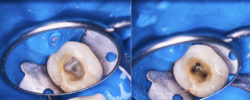

SLIKA A

Nakon davanja anestezije stavljen je koferdam. Kreiran je pravolinijski pristupni kavitet. Ovo je bilo moguće zbog velike kompozitne restauracije. Očuvanje restauracije nije imalo smisla jer je morala biti uklonjena i zamijenjena zbog marginalnog curenja. Traženje kanalnih šupljina i redefinisanje zida urađeni su ultrazvučnim vrhom Cavi (VDW).

SLIKA B